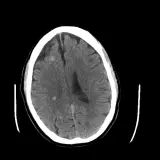

Over 2,100 interactive radiology cases, curated by radiologists for your level of training. Scroll, window, and view cases full screen — just like on PACS. Click linked findings in each writeup to jump straight to them on the image. Cases include sample reports, a focused discussion section, original illustrations, and videos.

PACSで期待されるツールを完備した完全インタラクティブな症例 — スクロール、ウィンドウ調整、ズーム、パン、計測、ROI、フルスクリーンモード。

重要な所見を症例画像上に直接ハイライトする豊富なアノテーション。症例解説内のリンクされた所見をクリックすると、スキャン上の正確な位置へジャンプできます。

アノテーション付きの画像所見とイラストで効率的に学習